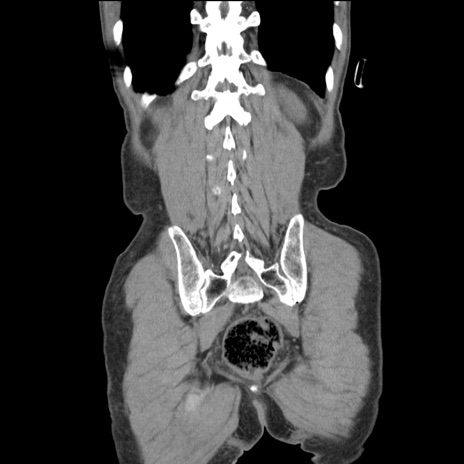

症例11(冠状断像)

【症例】 60歳代男性

【主訴】 下腹部痛

【現病歴】 本日夜中より下腹部痛の症状認め、受診。

【既往歴】 膀胱癌(膀胱全摘+尿管皮膚瘻術) 、胃癌術後

【身体所見】 BT 35.3℃、PR 58/min、BP 136/98mHg、腹部平坦、軟、腸蠕動音±、ストマ留置あり、左上腹部~正中部に圧痛あり、反跳痛なし。

【データ】WBC 5100、CRP0.01